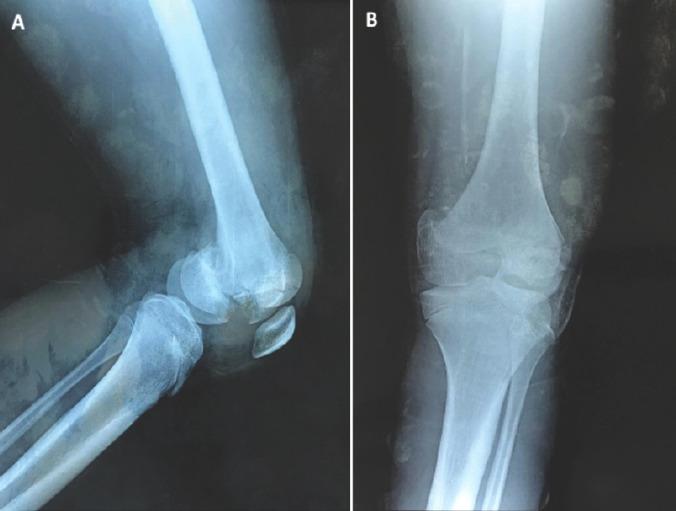

Our case report is focused on a 12-year-old patient victim of a high-impact trauma causing a bicondylar Hoffa fracture. The diagnosis was based on an X-ray in front and lateral views and confirmed by a computed tomography scan and 3D reconstructions. A screw fixation truth open reduction with a lateral approach. We report the satisfactory results of our case after a 24-month follow-up with a good range of motion.

我们的病例报告聚焦于一名12岁的患者,其因高能量创伤导致双髁霍法骨折。诊断基于前后位和侧位X线片,并通过计算机断层扫描和三维重建得以证实。采用外侧入路切开复位螺钉固定。我们报告了该病例在24个月随访后获得满意结果,关节活动范围良好。